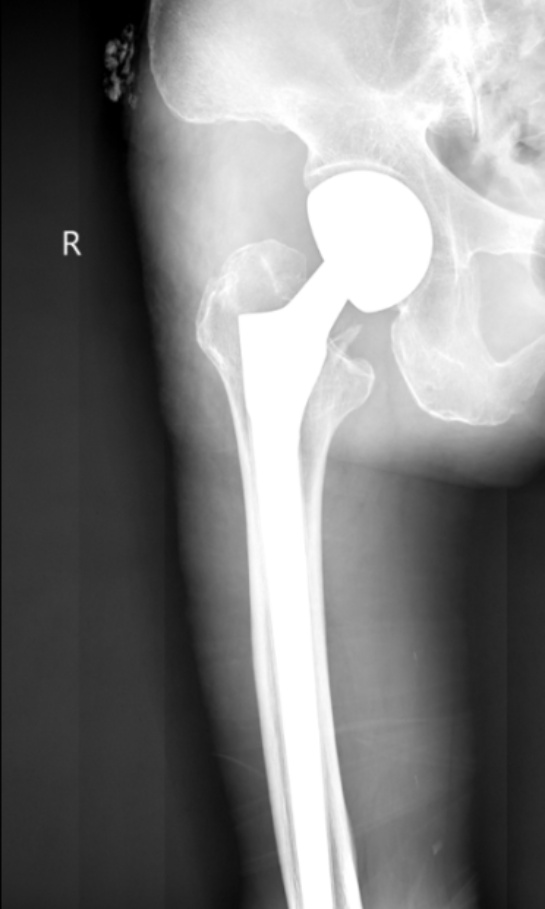

典型病例影像学表现见图1~10。图1为86岁女性右侧股骨转子间骨折(Evans Ⅲ型)患者,术前X线示骨折断端部分错位,术后X线示骨折位置可以及假体位置良好;图2显示了一名81岁男性患者,诊断为左侧股骨转子间骨折,类型为Evans V型,合并股骨干陈旧性骨折。患者接受了生物型加长柄半髋关节置换手术,并进行了股骨近端的钢丝捆扎内固定。术后X线示假体位置良好,股骨近端予钢丝捆扎固定;图3为87岁女性左侧股骨转子间骨折(Evans V型)患者,术后X线示假体位置良好,股骨大小转子骨折位置可,钢丝捆扎固定在位有效;图4为75岁女性左侧股骨转子间骨折(Evans V型)患者,术前X线示左侧股骨转子间骨折PFNA术后、骨折未愈合、内固定断裂。术后假体匹配良好,股骨近端钢丝内固定稳定可靠;图5为75岁男性左侧股骨转子间骨折(Evans IV型)患者,术后股骨大转子出现轻度位移,假体位置正常。图6为87岁男性左侧股骨转子间骨折(Evans V型)患者,给予DAA入路加长柄半髋关节置换,术前X线片,清晰地显示出左侧股骨转子间的骨折情况,术后X线影像,显示股骨的大小转子骨折位置良好,钢丝内固定装置在位稳定,假体位置良好;图7为77岁女性右侧股骨转子间骨折(Evans V型)患者,术前X线片显示右侧股骨转子间存在骨折且股骨大小转子均有累及和移位,术后X线片显示股骨小转子轻度移位,内固定装置位置稳定,假体位置良好;图8为70岁男性左侧股骨转子间骨折(Evans III型)患者,术前的X线片,清晰地显示了左侧股骨转子间的骨折情况,股骨近端髓腔钙化灶,术后假体位置满意;图9为77岁女性右侧股骨转子间骨折(Evans V型)患者,术前X线片,显示右侧股骨转子间及转子下部位骨折情况。术后假体匹配良好;图10为71岁男性右侧股骨颈骨折(Evans IV型)患者,术前X线片,显示右股骨转子间骨折的情况;术后X线表明股骨的大转子和小转子骨折位置保持良好,内固定装置稳固,术后假体位置正常。

Figure 1. 86-year-old female patient with right intertrochanteric fracture of femur (Evans type III). (a) Before surgery; (b) After surgery

1. 86岁女性右侧股骨转子间骨折(Evans Ⅲ型)患者。(a) 术前;(b) 术后